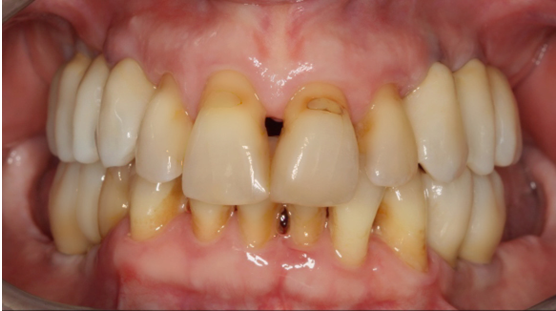

13. Θεραπεία χρόνιας περιοδοντίτιδας

Ασθενής ετών 50 προσήλθε στο ιατρείο με κύρια ενόχληση την αιμορραγία των ούλων και τη μετακίνηση των δοντιών. Οι περιοδοντικοί ιστοί ήταν ρόδινοι και εντοπισμένα ερυθροί, ενώ οι μεσοδόντιες θηλές διογκωμένες. Πολλά δόντια εμφάνιζαν υφιζήσεις, ενώ χαρακτηριστική ήταν η υπερέκφυση και απόκλιση του πλαγίου τομέα άνω αριστερά.

Παράλληλα με την περιοδοντική θεραπεία έγινε η αφαίρεση των παλαιών προσθετικών εργασιών και τοποθέτηση νέων μεταβατικών (προσωρινών) αποκαταστάσεων. Μετά τη μη χειρουργική θεραπεία παρατηρείται απουσία φλεγμονής.

ΑΡΧΙΚΗ ΚΛΙΝΙΚΗ ΕΙΚΟΝΑ

ΤΕΛΙΚΗ ΚΑΤΑΣΤΑΣΗ